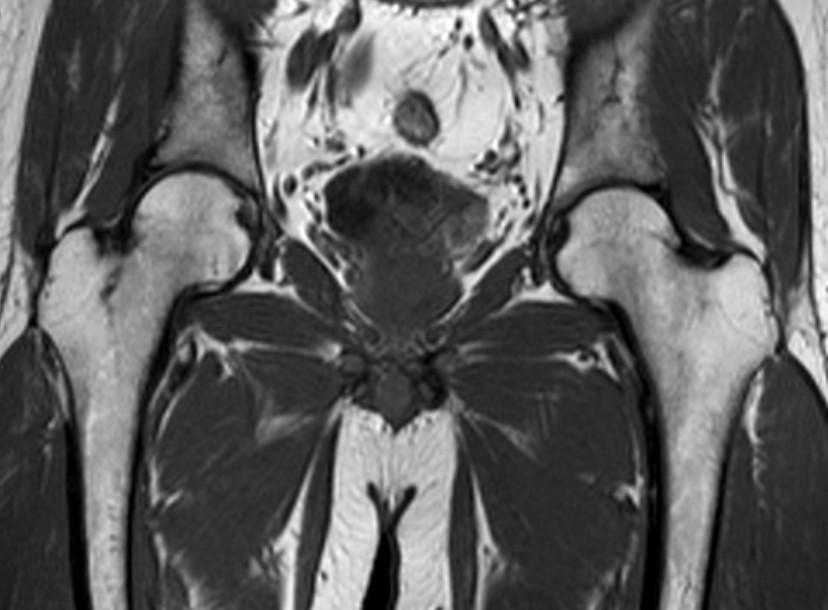

髋关节-T1